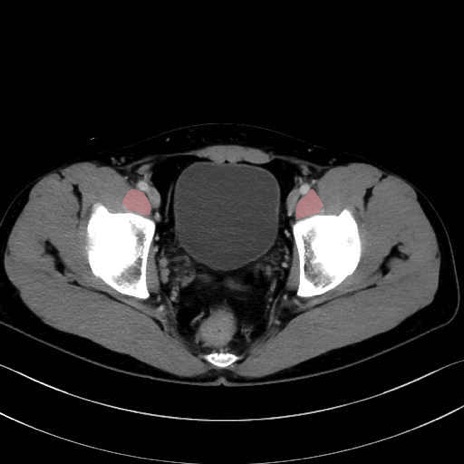

4. 深層外旋六筋(股関節の深部)

梨状筋 (Piriformis)

内閉鎖筋 (Obturator internus)

外閉鎖筋 (Obturator externus)